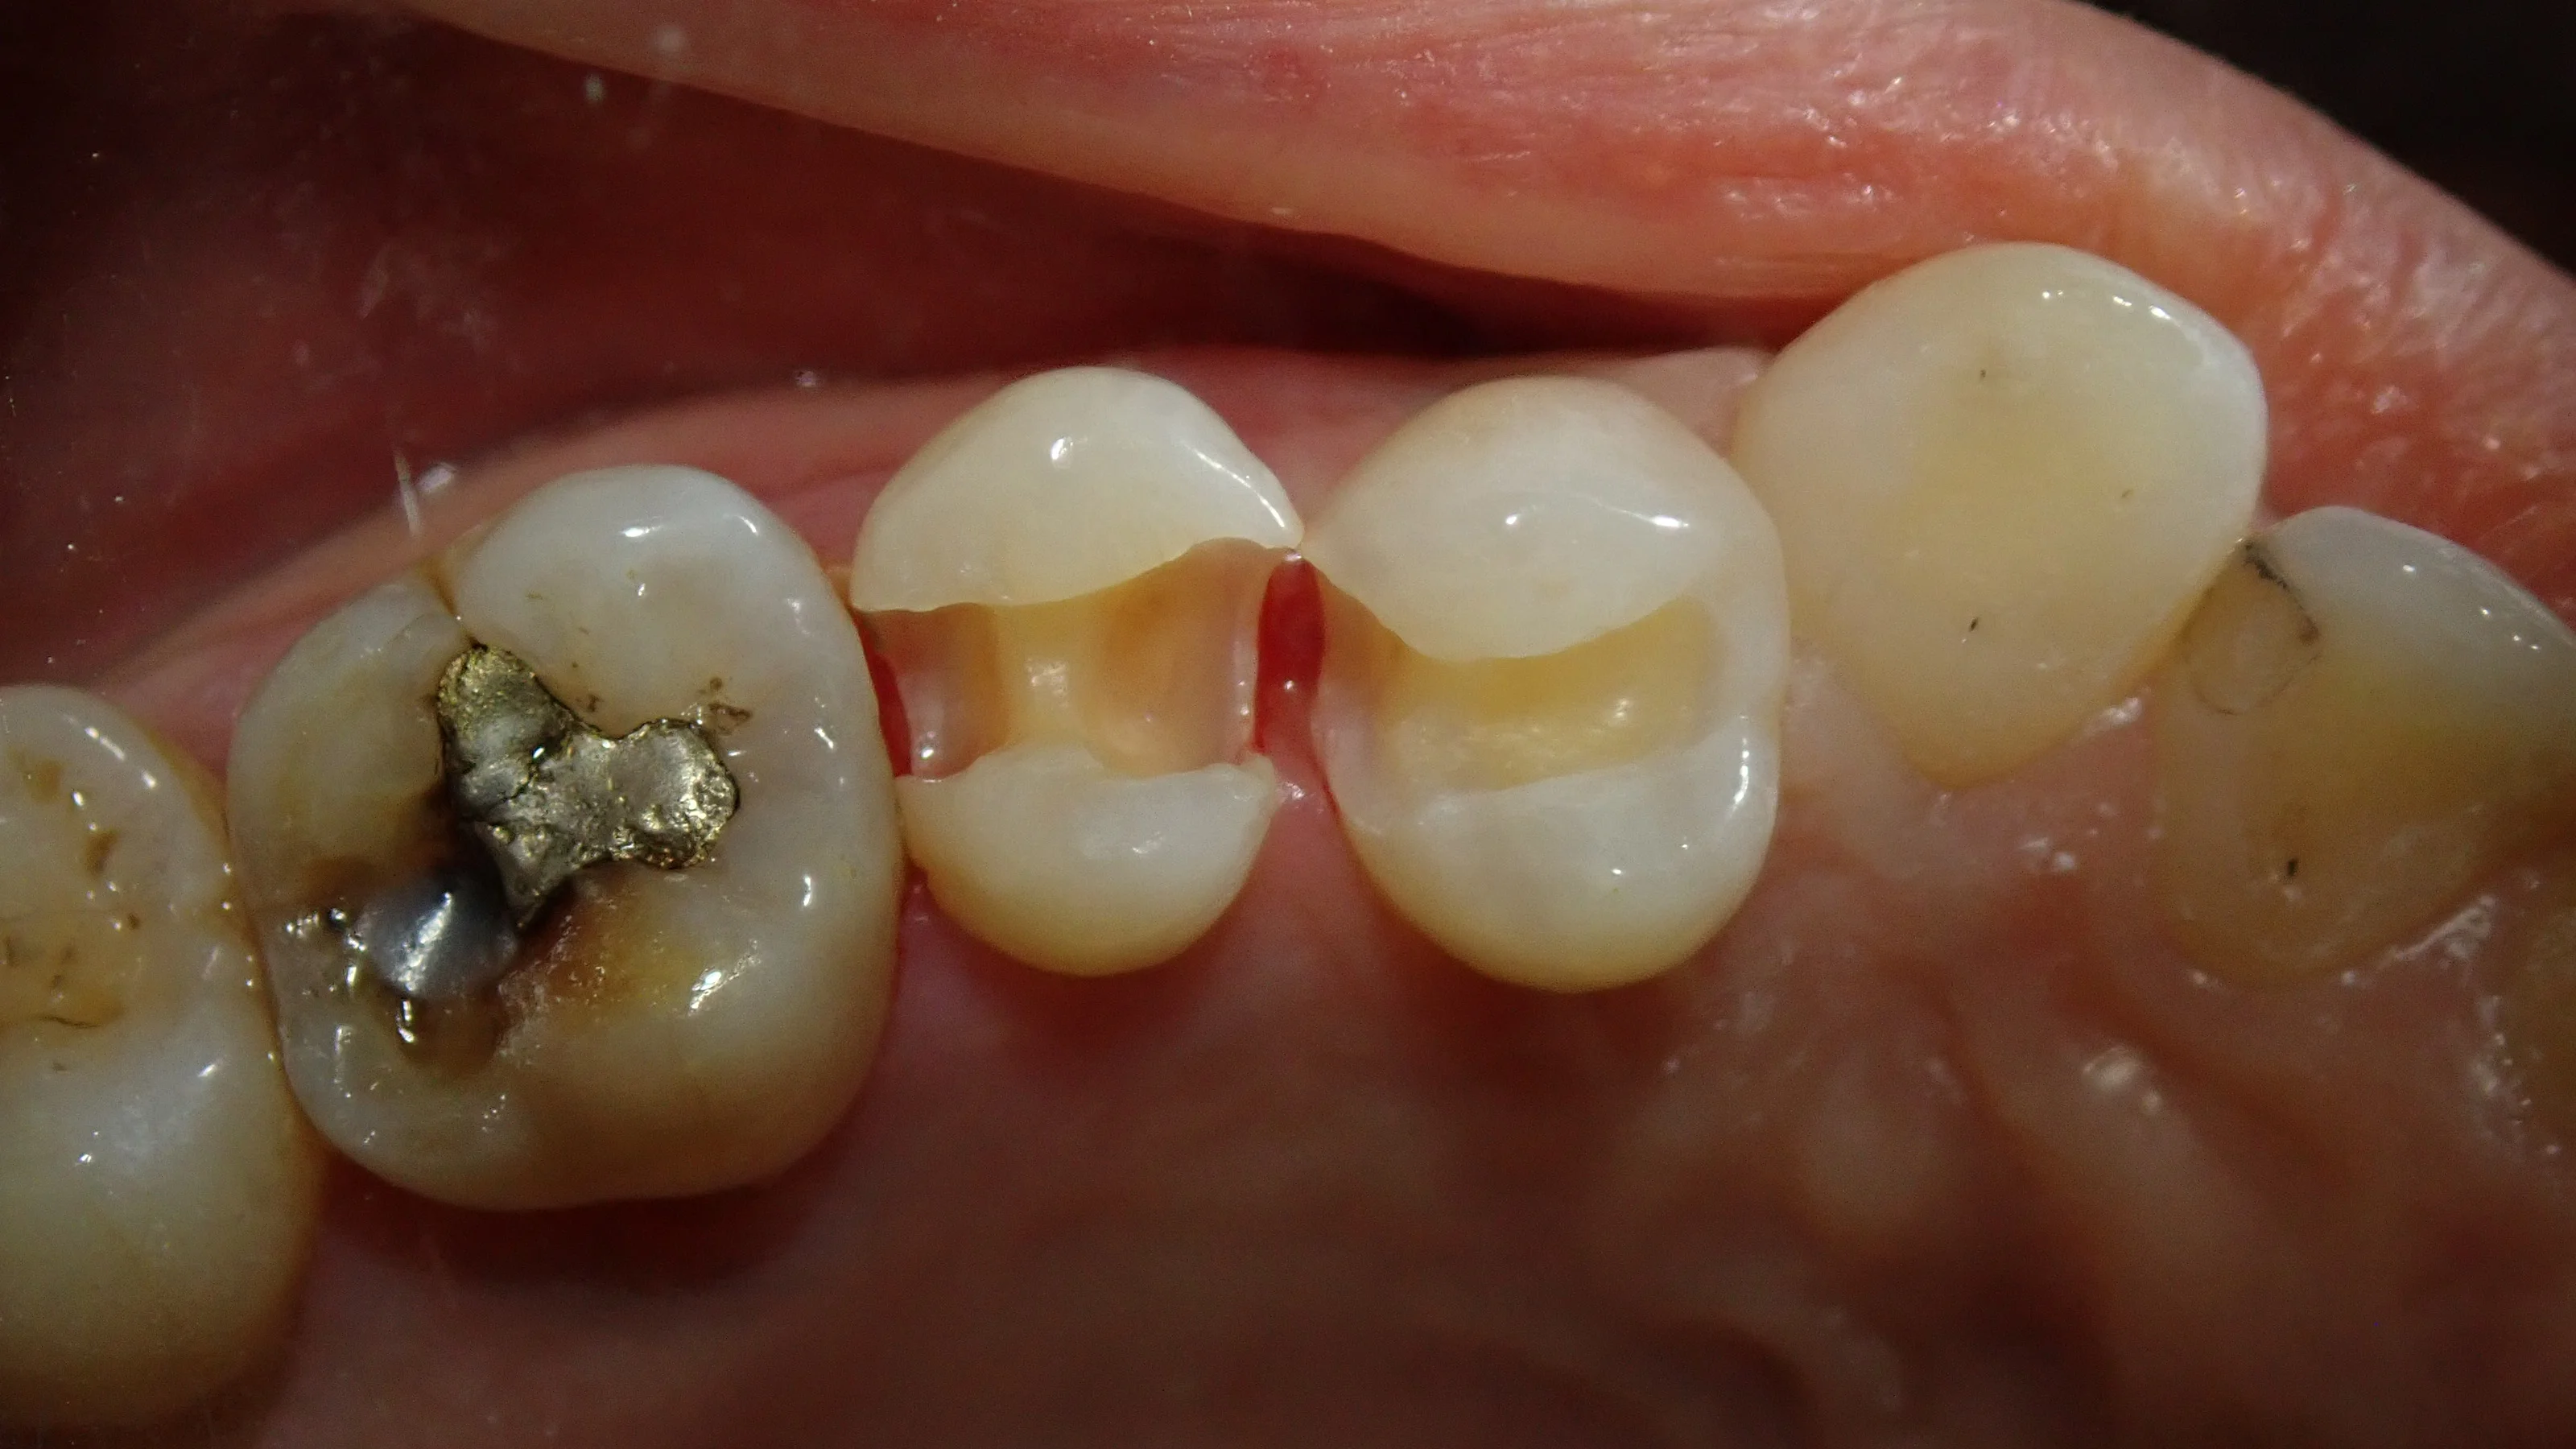

取り除いた後の画像がこちらです。

歯の色が全然違うのが分かるかと思います。

そして、歯茎ギリッギリで、合っていないCRが入っていたため、歯石がべったりと付いていました。

白い詰め物を詰める前に歯石を綺麗に取っておかないと「詰めたもの」と「歯」との間に段差が出来てしまい、結局直ぐにダメになってしまいます。

歯茎ギリギリまで虫歯になっていたので、歯石を取る段階で結構出血してしまいました・・・。